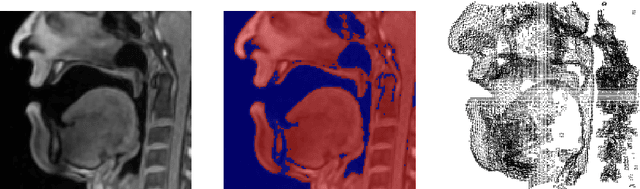

Abstract:We describe a minimally-supervised method for computing a statistical shape space model of the palate surface. The model is created from a corpus of volumetric magnetic resonance imaging (MRI) scans collected from 12 speakers. We extract a 3D mesh of the palate from each speaker, then train the model using principal component analysis (PCA). The palate model is then tested using 3D MRI from another corpus and evaluated using a high-resolution optical scan. We find that the error is low even when only a handful of measured coordinates are available. In both cases, our approach yields promising results. It can be applied to extract the palate shape from MRI data, and could be useful to other analysis modalities, such as electromagnetic articulography (EMA) and ultrasound tongue imaging (UTI).